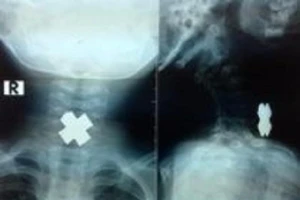

Lấy dị vật hình chữ thập trong thực quản bé trai 3 tuổi